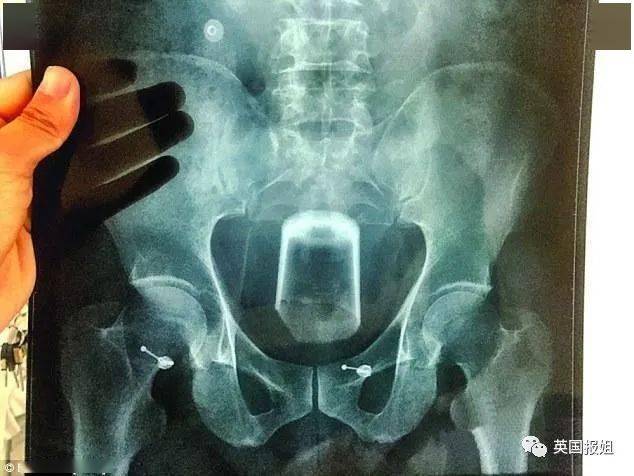

▷一个瓶子这位60岁男士同样是为了缓解便秘 , 才试着把瓶子塞进去“以毒攻毒” 。